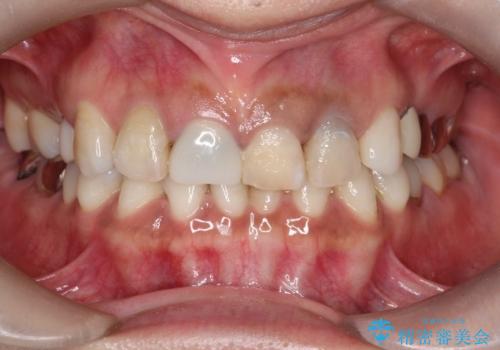

【オールセラミッククラウン】前歯を白くきれいにしたい。

- 前歯の変色を主訴に来院されました。

歯茎のラインも整っていなかったため、手術を行いきれいな被せ物をいれることができました。